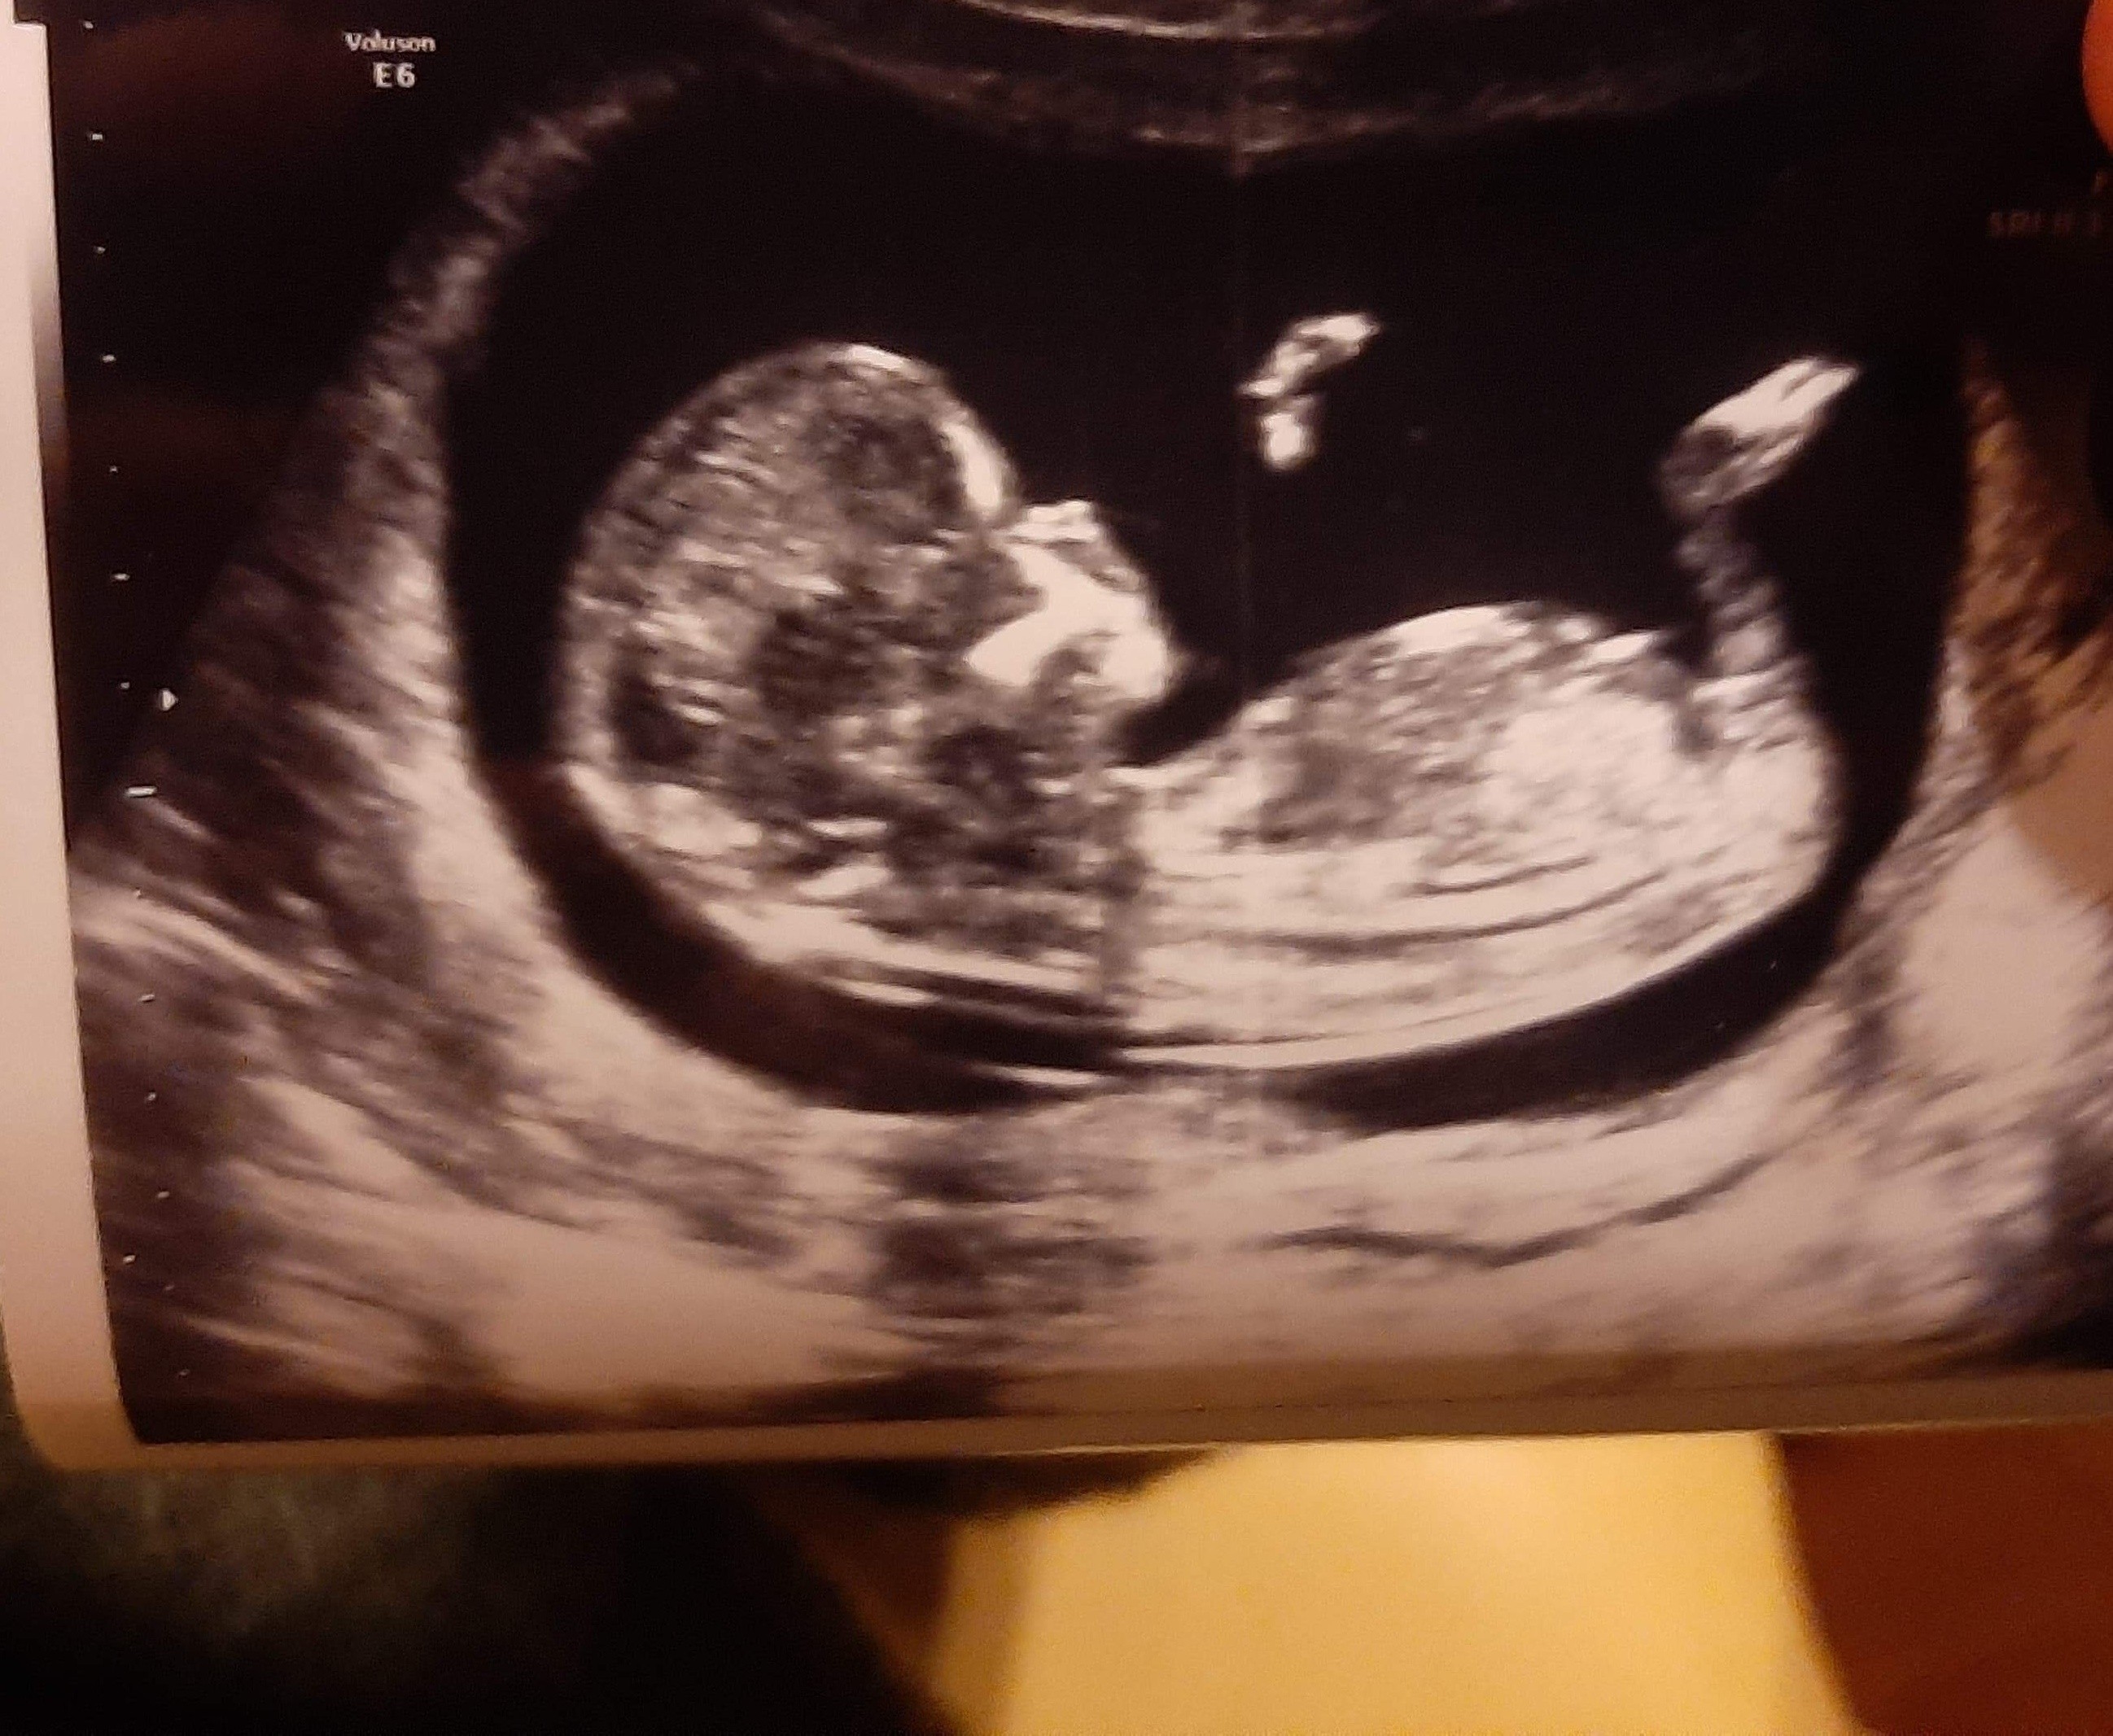

12tc. USG, chłopak czy dziewczyna?

Cześć dziewczyny, mam zdjęcia USG z 12tc+3d, podobno można stwierdzić płeć po wyrostku. Co myślicie? dziękuję za każdą odpowiedź

IMG_20191105_222148.jpg